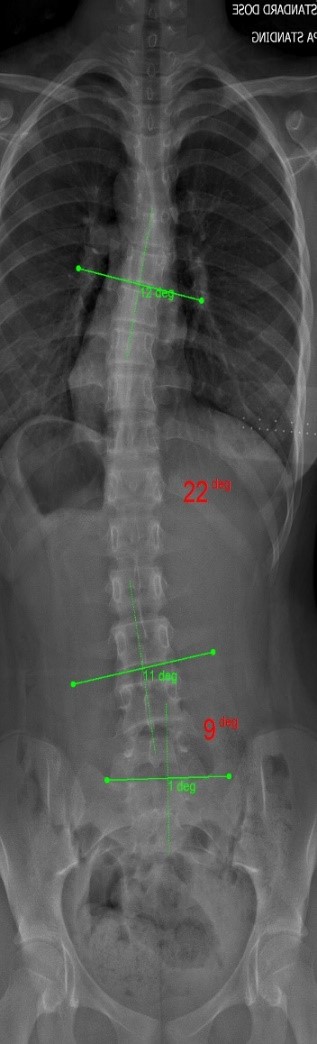

The clinical test results show that the SCN800 series is highly consistent with the X-ray, with a linear correlation of 0.94, similar results have also been published in SCI articles (Lee TT, Lai KK, Cheng JC, Castelein RM, Lam TP, Zheng YP. 3D ultrasound imaging provides reliable angle measurement with validity comparable to X-ray in patients with adolescent idiopathic scoliosis. Journal of Orthopaedic Translation. 29:51-59, 2021).

In our clinical trials and studies, we measured two angles to facilitate comparison. X-rays can actually show 3 to 4 angles, some in the neck and bottom area. Ultrasound images can also measure angles near the neck like an X-ray.

The following images compare 5 ultrasound and X-ray clinical measurement examples: